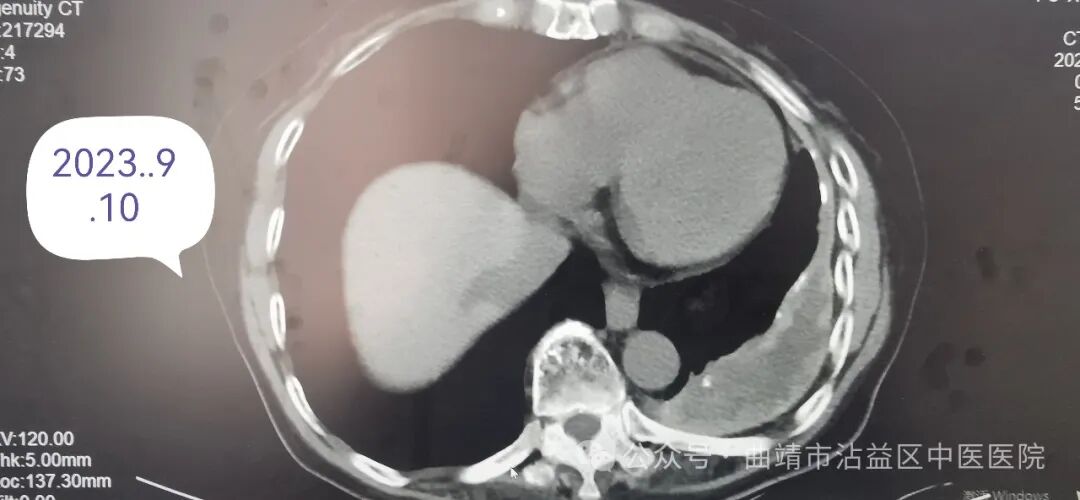

患者女,71岁,因“反复咳痰喘、痰中带血5年余,加重2天”至我院就诊,患者曾多次在曲靖市级,沾益区县级住院治疗,行胸部CT提示“左肺包裹性积液”,经治疗症状可得到部分缓解,但发热、盗汗、乏力、咯血等症状反复,诊断不明。收入我院肺病科后,行气管镜检查,肺泡灌洗后送检发现复合结核杆菌阳性,确诊为继发性肺结核。经我院肺病科医师团队行抗结核治疗后无痰中带血,相关症状好转,出院后继续规律抗结核治疗,后经随访病情已经好转。电子支气管镜、肺功能监测仪、多导睡眠监测仪、高流量治疗仪、无创呼吸机、有创呼吸机、除颤仪、床旁心电监护仪等呼吸系统先进诊疗设备。运用中西医结合方法治疗急慢性阻塞性肺疾病、慢性肺源性心脏病、肺动脉栓塞、肺恶性肿瘤、肺间质纤维化、大叶性肺炎、社区获得性肺炎、重症肺炎、感染中毒性休克、呼吸性细支气管炎、闭塞性细支气管炎、支气管哮喘、咳嗽变异性哮喘、肺结核、肾功能不全、急性肾盂肾炎、慢性肾炎、即将开展肾血液透析及血小板减少、贫血、过敏性紫癜等疾病。开展穴位贴敷、中药塌渍、中频治疗、红外线治疗、拔罐、针灸等特色中医治疗项目,以西医诊断、中医辩证、运用中西医结合的方法诊疗呼吸系统、泌尿系统、血液系统疾病具有较强的诊治能力和独特的疗效。